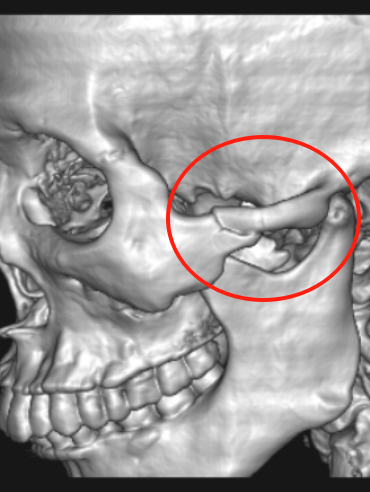

门诊行颌面部CT检查的结果显示:左侧颧骨骨折,像被摔碎的瓷器般塌陷移位;上颌窦外侧壁骨折颧骨体多处骨折,骨片如飘零的落叶游离在外;窦腔少量积血,软组织积气。

术中发现颧骨体多发骨折伴内下移位,上颌窦外侧壁骨折伴游离骨片。以解剖标志为导向精准复位后,植入钛板及数枚螺钉固定。